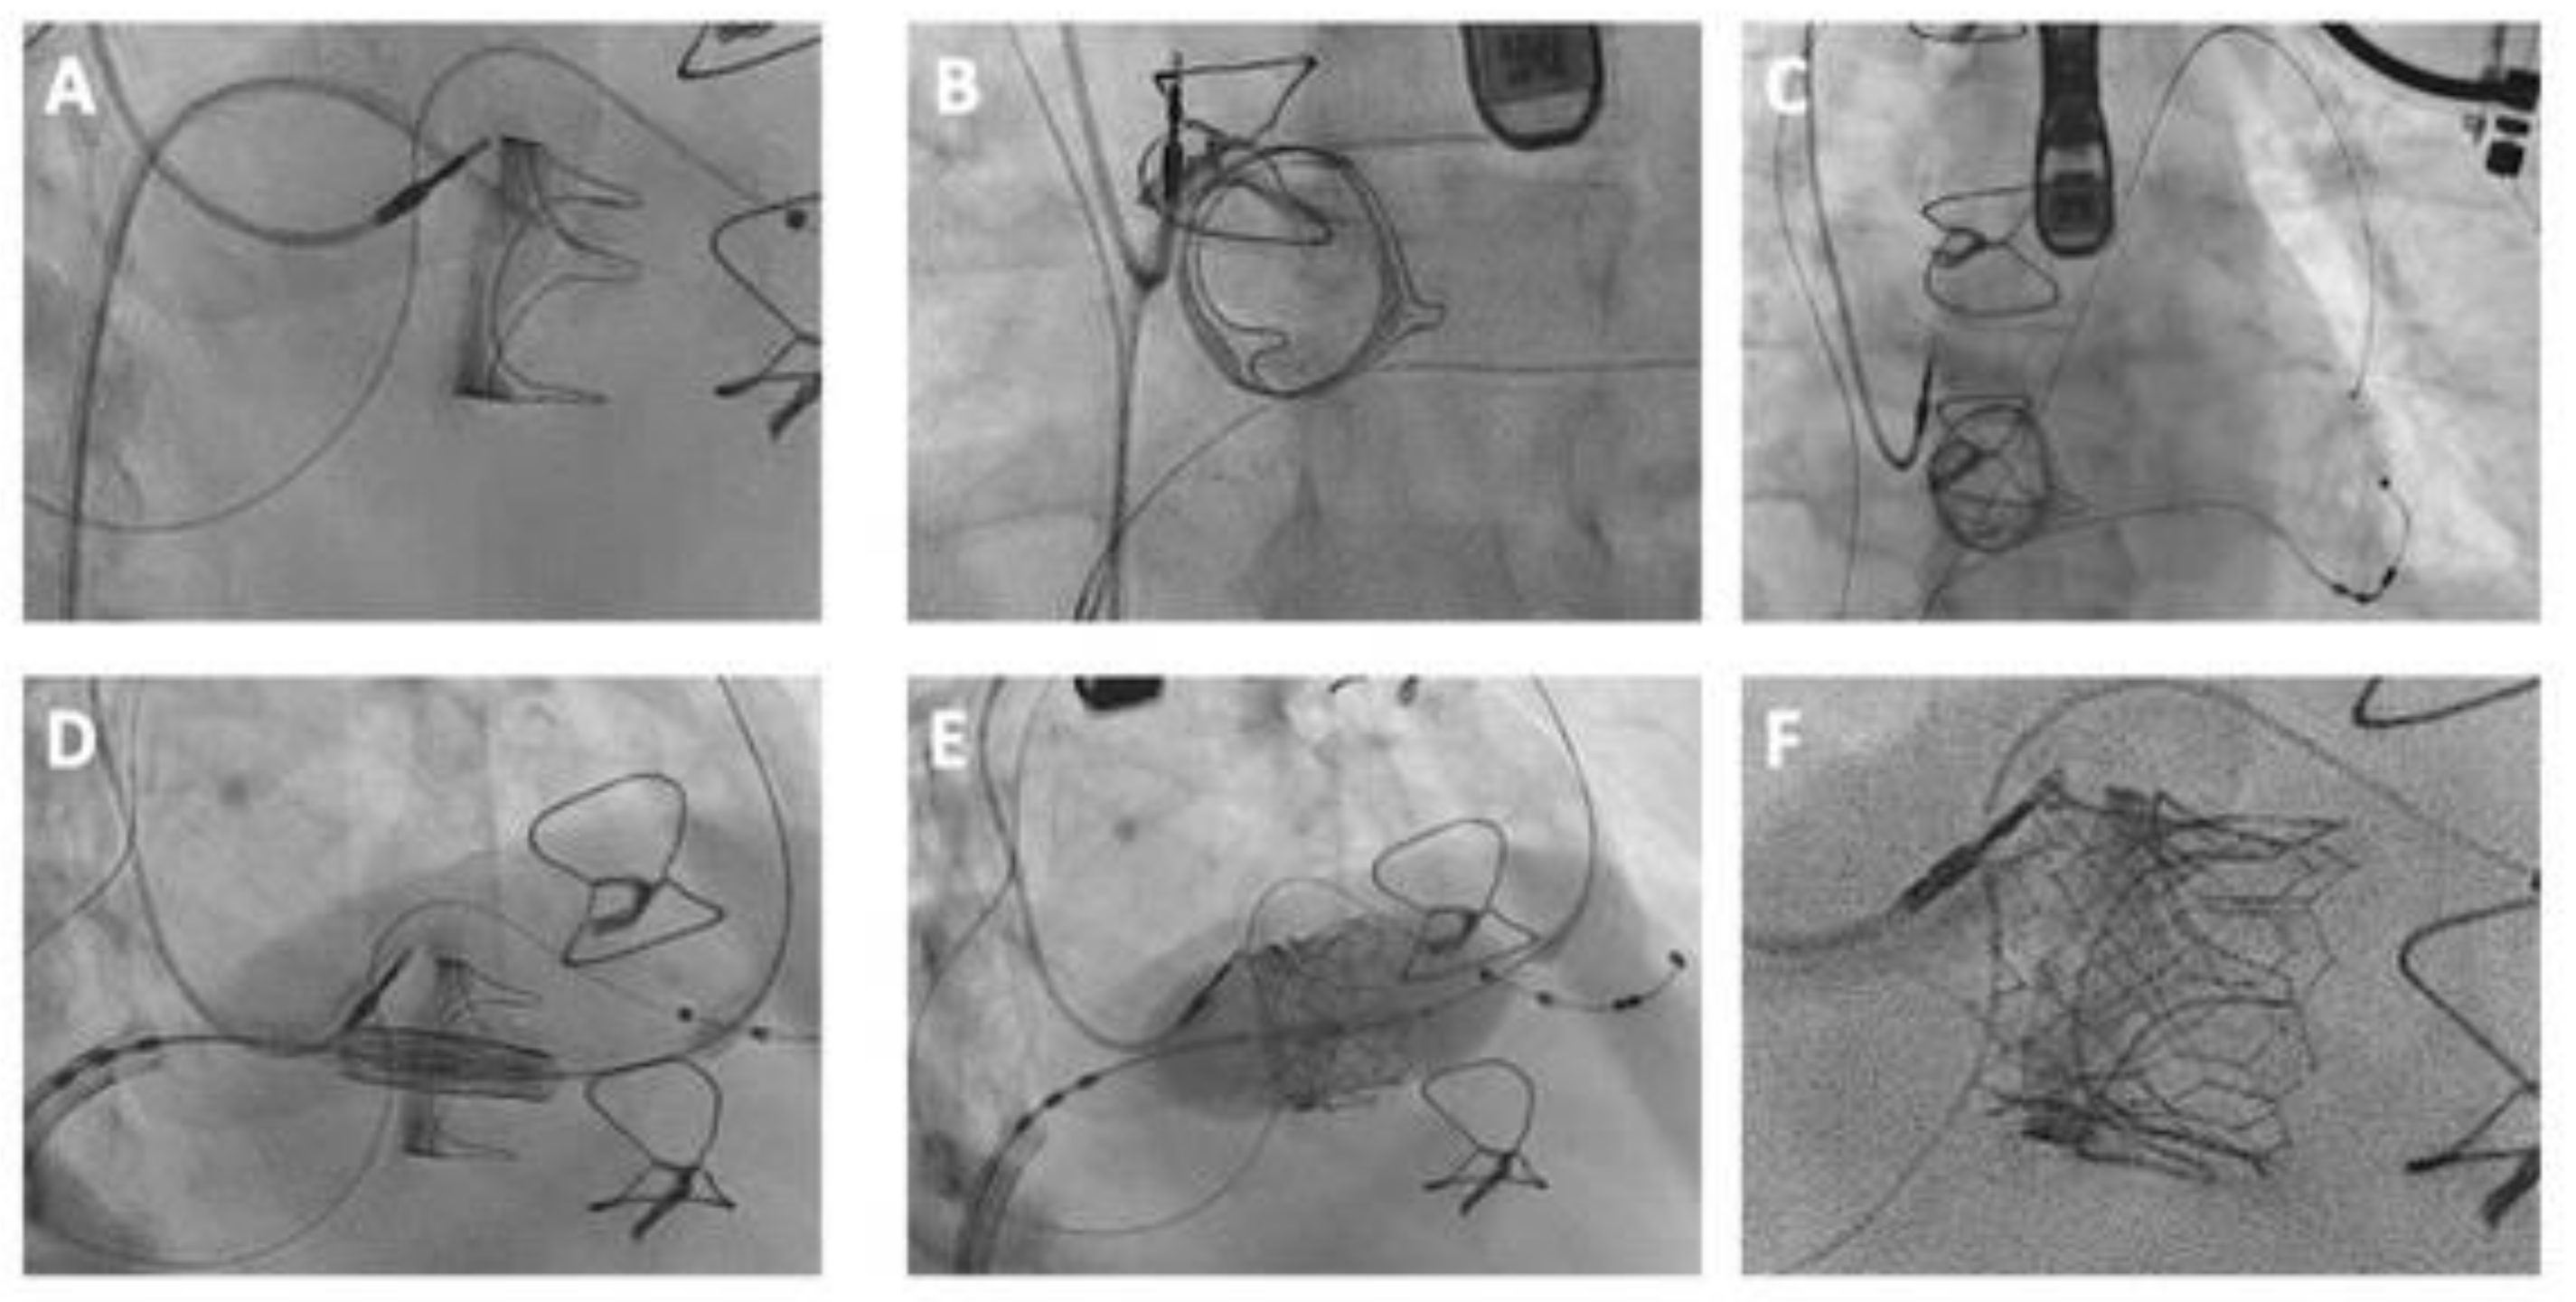

Figure 4.

Planning and performing a redo-TAVI procedure. An example of a redo-TAVI procedure where a balloon-expandable Sapien S3 Ultra (Edwards Lifesciences, USA) TAV was used to treat a degenerated self-expandable Evolut R 34 mm TAV. (A) Presence of heavy calcification located at the right cusp (green dot) and left cusp (red dot) contributed to underexpansion of the first TAV, which impacts the (B) sizing strategy of the S3. (C) A low implantation targeting node 4, was deemed safe to prevent coronary obstruction. (D–F) Fluoroscopic images demonstrating the (D) extent of regurgitation pre-procedurally, (E) targeting node 4 (white arrow) and (F) final result confirming patency of both coronary ostia (represented by stars).